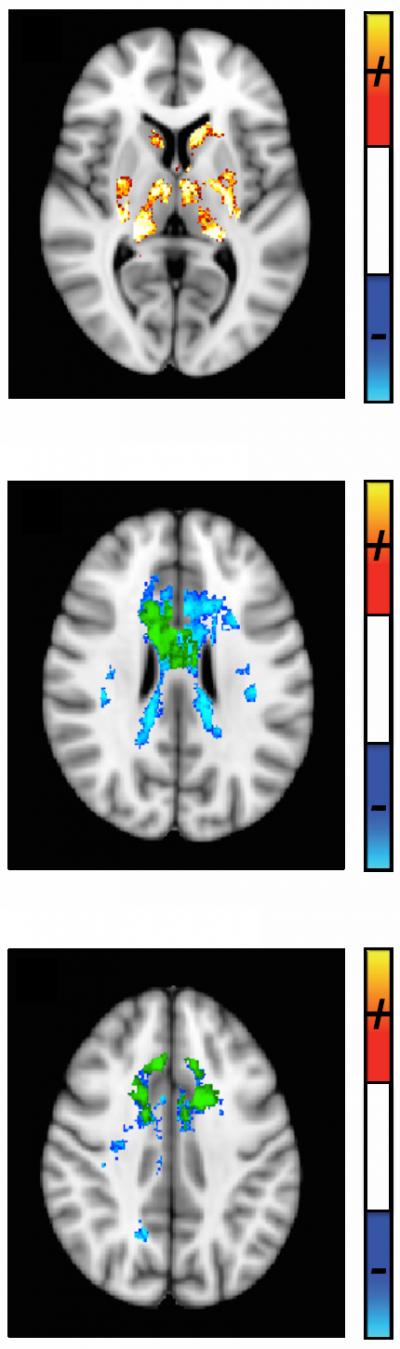

Imaging scientists at Western University's Robarts Research Institute (London, Canada) have developed a better way to track the progression of Multiple Sclerosis (MS) from its earliest stages. Led by Ravi Menon, PhD, the researchers used what's called "Quantitative Susceptibility (QS) Magnetic Resonance Imaging (MRI)," to measure damage in specific areas of the brain which the study showed to be common to all patients. The findings are published in advance online, in Radiology .

The process used a standard Siemens 3T MRI so it could be reproduced in any hospital, using the technique, called QS. The researchers mapped this MRI parameter in 25 patients with relapsing-remitting MS or clinically isolated syndrome (CIS –half of those diagnosed with CIS will go on to be diagnosed with MS) measuring both demyelination and iron deposition. Fifteen age and sex-matched control subjects were also scanned. While brain and spine lesions visualized with normal MRI tend to appear and disappear over time, QS shows common areas of damage in all patients that correlated very well with the Extended Disability Status Score (EDSS) which is a standard tool used to measure MS progression, as well as with age and time since diagnosis.

"Significantly, in white matter, even where we see no lesions whatsoever, we're able to measure damage in the same area of all patients using QS mapping. So even at the very earliest stages of the disease when the disability score is very low, or when the person hasn't yet been diagnosed with MS, there's already significant damage," adds Menon. This could have important diagnostic and prognostic implications, as there are drugs available to slow or stop the progression of MS, if started early enough.